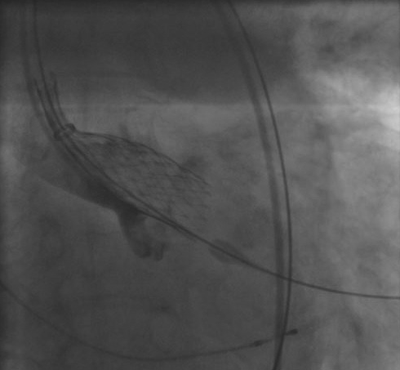

Nach gründlicher Untersuchung stand fest: Herta Grulichs Aortenklappe schleuste das Blut statt durch eine mehr als 2,5 Quadratzentimeter große Öffnung nur noch durch bedenkliche 0,6 Quadratzentimeter. Die Mediziner entschieden sich, die Herzklappe interventionell (also mit einem Herzkatheter) zu ersetzen. Die Methode ist relativ neu und wurde bislang nur an Universitätskliniken angewandt. Dabei wird ein etwa bleistiftdicker Schlauch durch ein Blutgefäß in der Leiste bis in das Herz geführt. Dort angekommen, entfaltet sich die neue Herzklappe aus biologischem Material wie eine Feder und nimmt sofort die Arbeit auf.